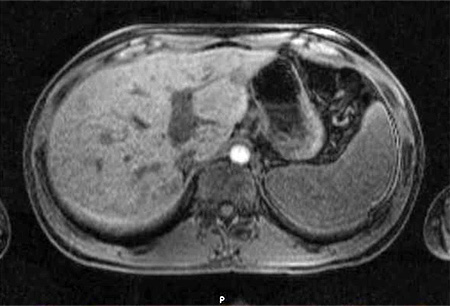

cat scratch disease  Cat-scratch disease | Radiology

Cat-scratch disease | Radiology  Cat Scratch Disease and Your Child